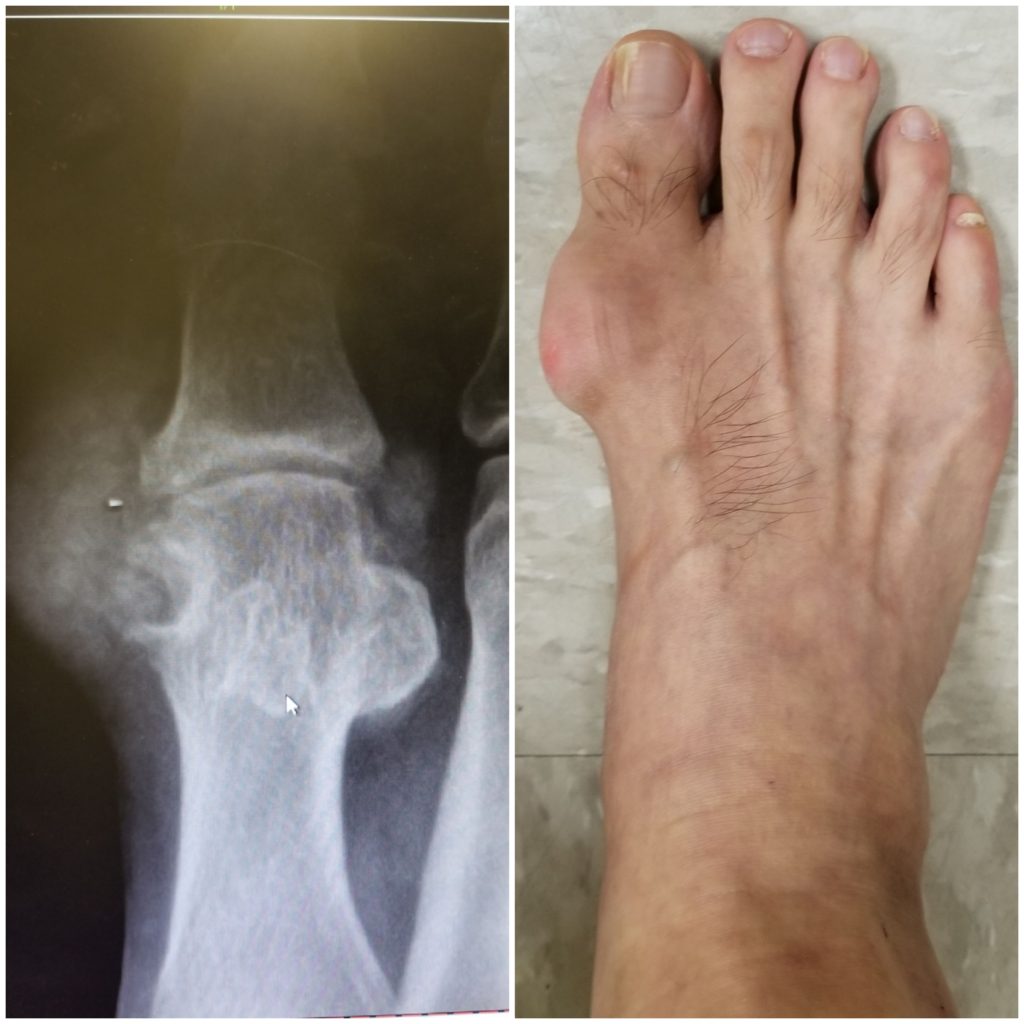

From www.jfas.org

Intraosseous Gouty Tophus in the Talus A Case Report The Journal of Foot Surgery For Gout Reduce or even eliminate your intake of meat and shellfish, both of which can raise uric acid levels. because tophaceous gout can cause irreparable damage to your joints, one of three surgical treatments is often. an acute gout attack is treated with medication and does not require surgery. a gout attack can cause extreme pain. diet. Foot Surgery For Gout.

From www.reumatologiaclinica.org

Gouty Involvement of Foot and Ankle Beyond Flares Reumatología Clínica Foot Surgery For Gout However, sometimes when you have an acute gout attack, there is also a. an acute gout attack is treated with medication and does not require surgery. the main treatment for gout is medical management of acute inflammation and chronic uric acid levels, but surgical. Learn the common causes, symptoms and treatments from a top gout doctor at hospital. Foot Surgery For Gout.

Gout or degenerative osteoarthrosis/hallux limitus? Damien Lafferty Foot Surgery For Gout several surgical procedures for the foot and ankle in people with chronic tophaceous gout were reported. the main treatment for gout is medical management of acute inflammation and chronic uric acid levels, but surgical. However, sometimes when you have an acute gout attack, there is also a. Learn the common causes, symptoms and treatments from a top gout. Foot Surgery For Gout.